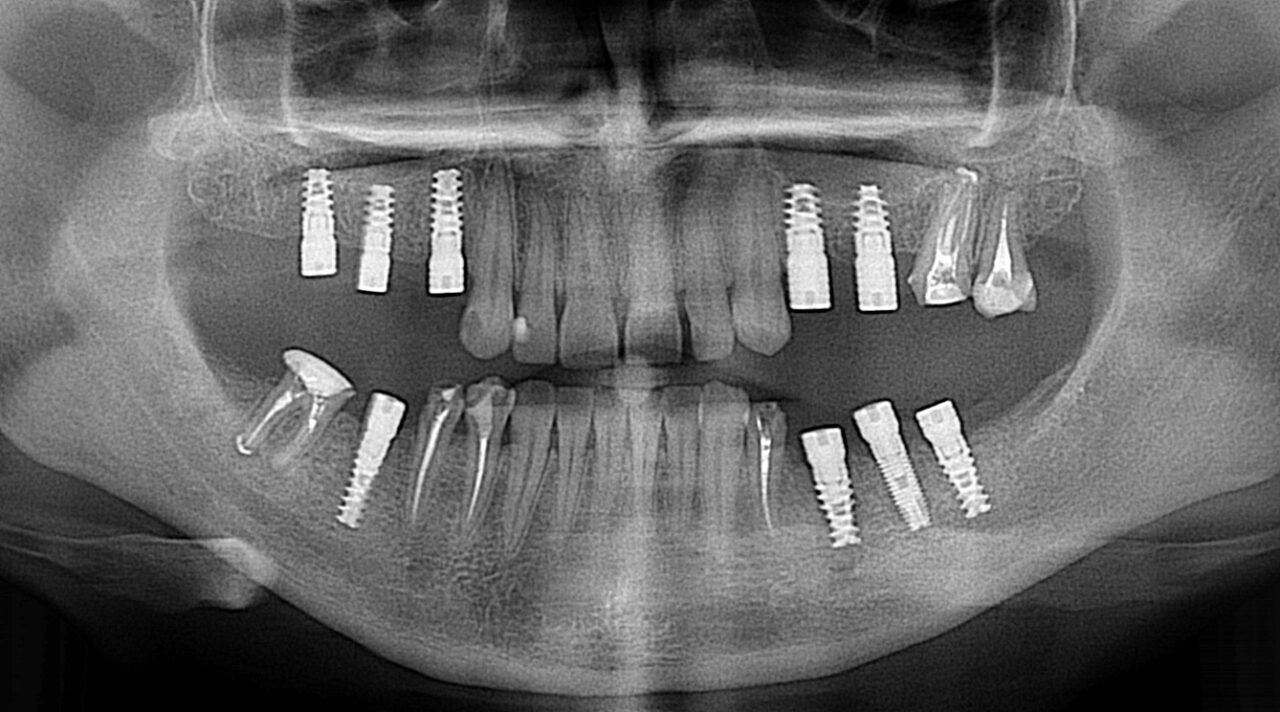

Підготовка до імплантації зубів – перший крок на шляху до відновлення зубного ряду. Клініка UkrDentClub пропонує пройти весь підготовчий процес, адже надає комплексні послуги з діагностики та лікування порожнини рота. Консультація в лікаря передбачає огляд, збір анамнезу й обстеження за допомогою безпечних технологій (рентгенографії, КТ). Підготовка включає розробку плану імплантації на основі даних про стан кісткової тканини, професійне чищення, лікування зубів та ясен за показаннями.